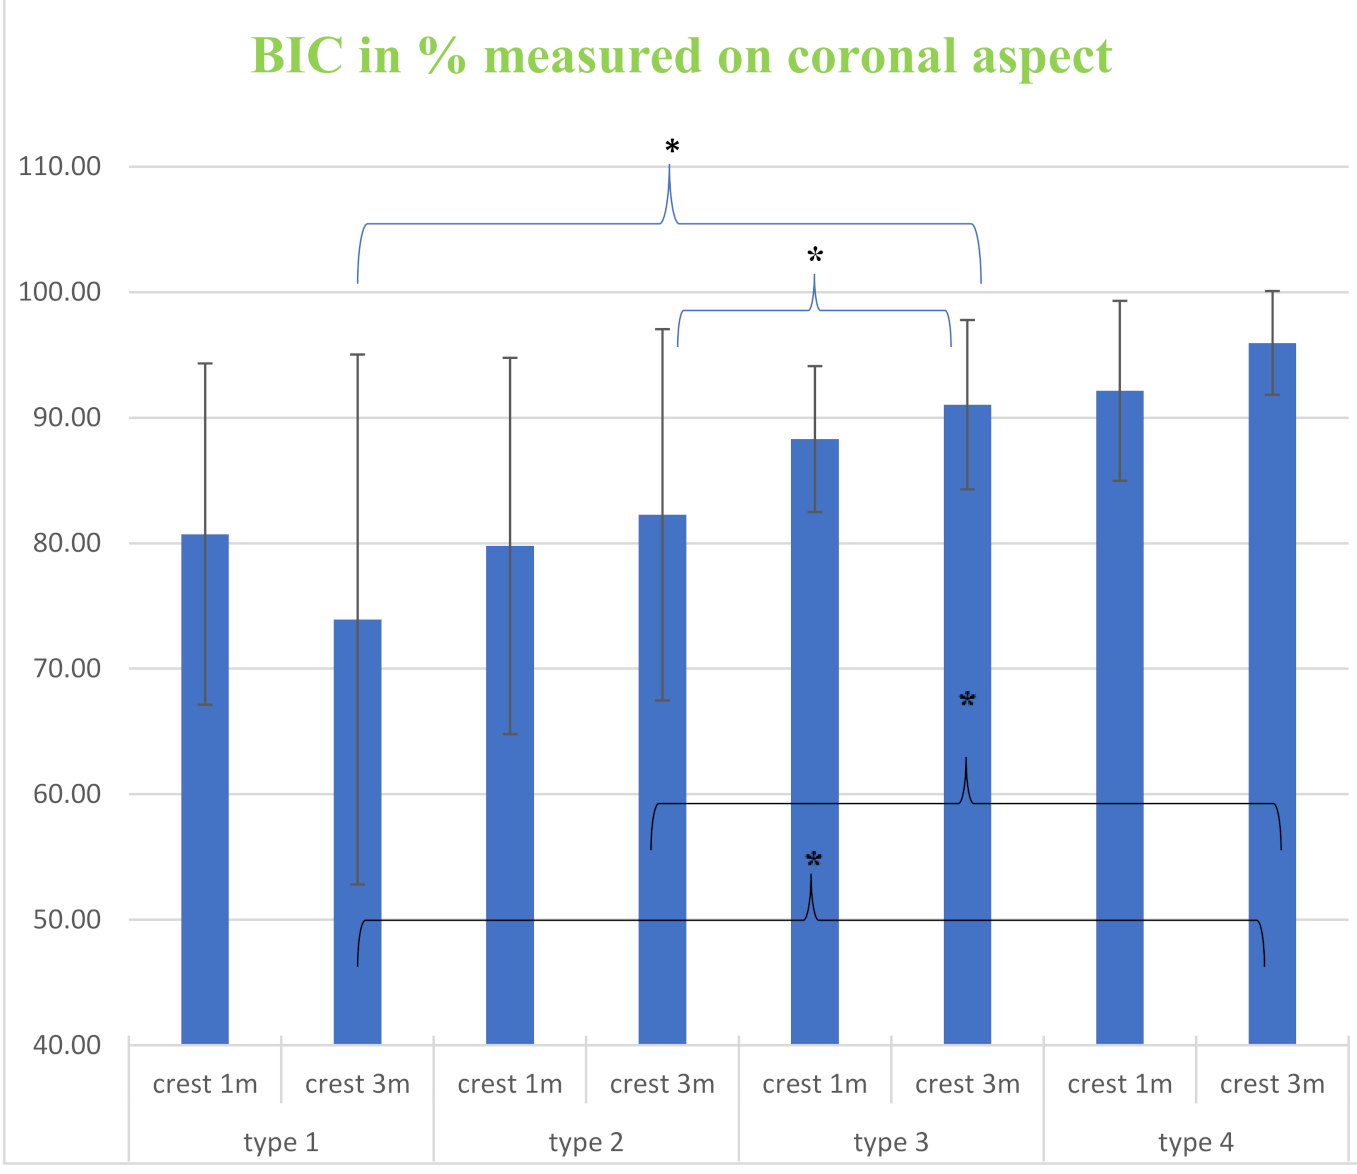

3. Results

| 1 month | 80.73 ± 13.60 | 79.78 ± 14.99 | 88.30 ± 5.81 | 92.15 ± 6.21 |

| 3 months | 73.92 ± 21.11 | 82.27 ± 14.79 | 91.04 ± 6.75 | 95.96 ± 4.13 |